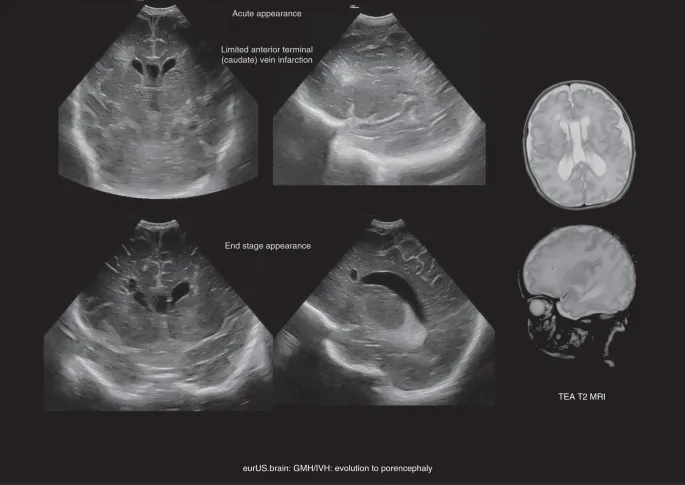

- Serial Cranial Ultrasound (CUS) monitoring.

- Cranial ultrasound is the gold standard for diagnosis, using Papile grading (I-IV) for severity.

- Complications: Post-Hemorrhagic Hydrocephalus (PHH), periventricular hemorrhagic infarction (PVHI - Grade IV), cystic Periventricular Leukomalacia (PVL), seizures, cerebral palsy, developmental delay.

- Prognosis: Grade-dependent. Grade I/II generally good; Grade III/IV ↑risk mortality & neurodevelopmental impairment.